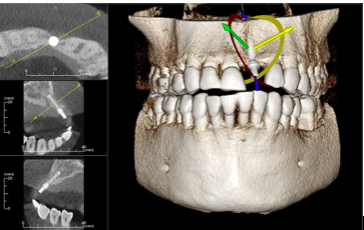

Dental implants

– Location of anatomic structures

– Size and shape of ridge, quantity and quality of bone

-Number, orientation of implants

-Need for bone graft, sinus lift

– Use of implant positioning software

The patient is precisely placed in a comfortable position at the machine. The scan takes about 20 seconds to rotate around the head, obtaining nearly 600 distinct images. The focused x-ray beam reduces scatter radiation, resulting in better image quality. Once complete, the 3D image is immediately available for viewing and diagnosing. The scan produces a wide variety of views and angles that can be manipulated to provide a more comprehensive evaluation. One CBCT scan uses about 1/20th the radiation of a traditional head and neck scan at the hospital.